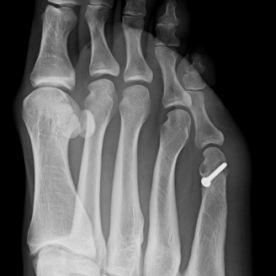

Röntgenbilder